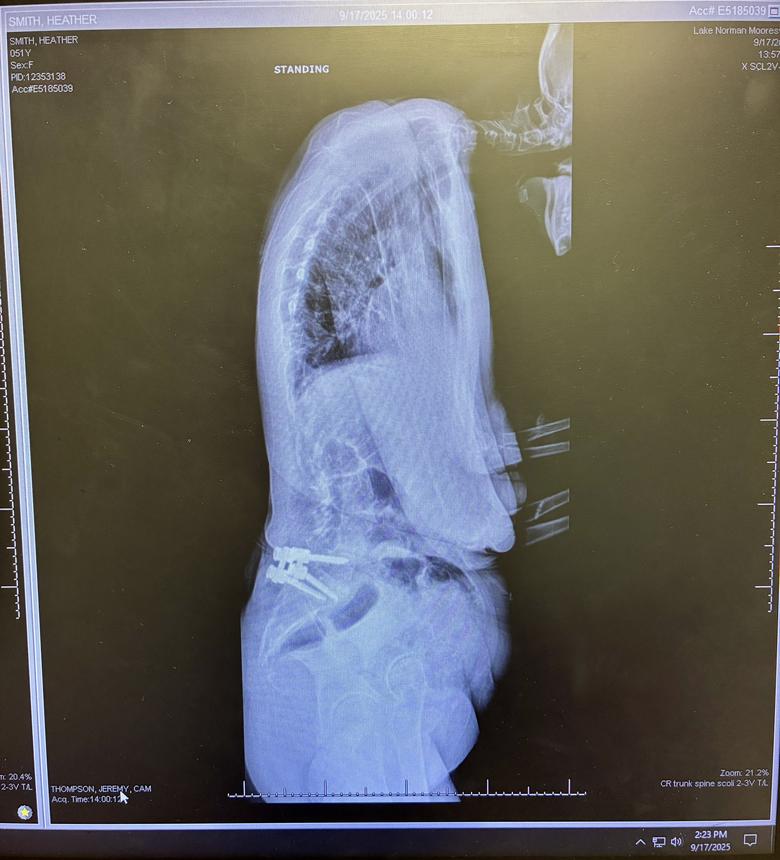

Everyone, I owe each and all of you a huge apology for just now getting back to you. Roughly 2 months ago, which was when I stopped posting, I started having very bad issues with my left hand which was later determined to be “trigger finger” on both my middle and ring fingers. It got to the point where those fingers were locking up on me and to move them from their position felt like I was trying to break them . I had literally lost the use of my left hand. Well last week, I had surgery on my hand to free up the tendons in my palm to prevent that from happening anymore. (*THE FOLLOWING VIDEO IS GRAPHIC!!*)https://vimeo.com/manage/videos/1130619627 ![]() ![]() However, I’m now bruised from the front side of my palm, to the back side of my palm, and basically feel like I’m constantly grabbing long needle cactus plants right where they cut me open 🫣 ![]() . ![]() ![]() I will have to keep bandages on it for 2 weeks straight (which you never realize how many things you depend on *2* hands for until you only have one!). I have been so reluctant to handle anyone’s books as I have been dropping things left and right. 🤦🏻♀️ . I’ve been petrified that I would damage something. But as soon as I get the bandages off and the use of my hand back, I’ll be able to start packing up books. I do have an update on my back, and it’s not good…it’s not good at all. I had new images taken, and these were the results: ![]() ![]() I started crying when I saw them. As you can see, my spine has collapsed much worse both sideways and forwards in just the past 2-3 years since my last imaging was taken. What’s worse, I’ve now been told that at best, I have perhaps another 7-8 years before I won’t be able to walk anymore (that’s assuming that the catastrophic heart failure side of Emery-Driefuss Muscular Dystrophy doesn’t get me first…and is it so wrong to kinda be rooting for that outcome?). Guys, every day I lose a little bit more will to keep going. I’m sorry, I really did just want to let everyone know what had been going on. But on a brighter note…I’ve set aside a bunch more books and slabs to sell if anyone is interested. Lord knows I won’t be needing them . |